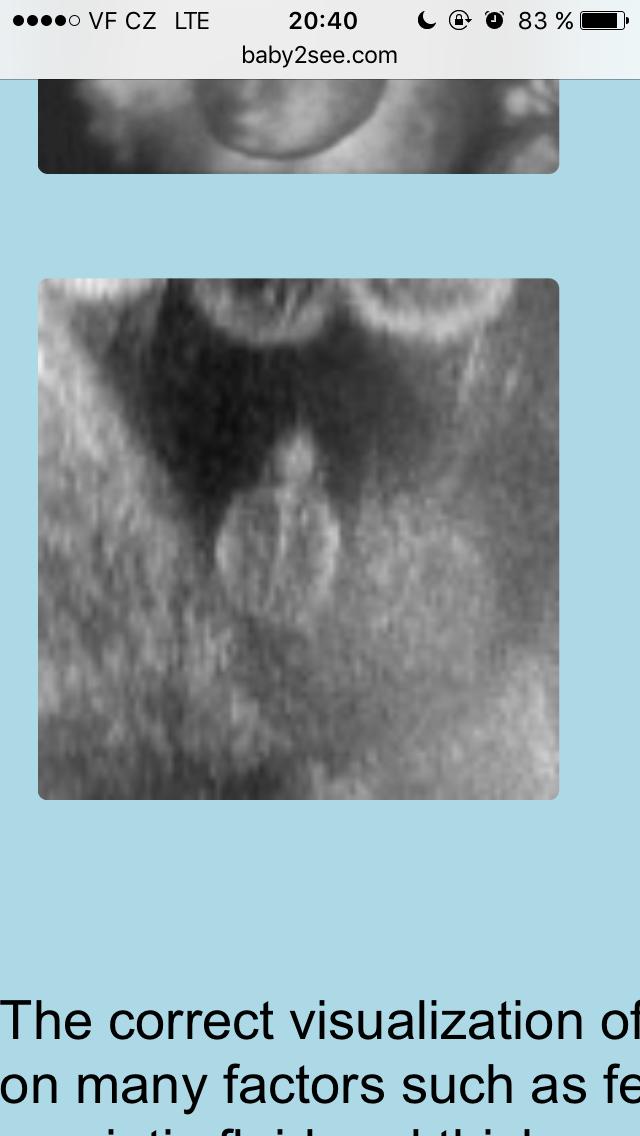

@snekule mne to tedy prijde jako kluk. Vsak je to vic pred telem,holcicka ve 25tt uz ma krasne videt zrno

@snekule koukni. Sice ty dva utz jsou uplne ciste a jasne viditelne. Ale vic bych se priklanela ke klukovi,kdyz to porovnas s tim svym utz